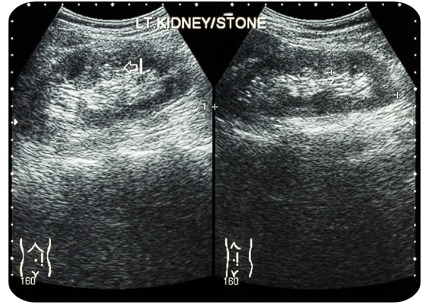

La ecografía renal permite evaluar de forma no invasiva la anatomía y condiciones funcionales de los riñones y vías urinarias. En QUIRULAP, este estudio es realizado con equipos modernos que garantizan imágenes de alta resolución para un diagnóstico confiable.

Cálculos renales